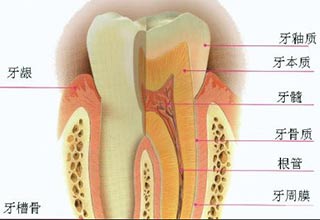

牙釉质是包裹在牙齿外层白色半透明的坚硬组织,牙釉质的密度坚硬程度受牙齿中钙含量的影响,而牙釉质的状态变化直接表现牙齿整体颜色和光泽度的变化。

牙釉质结构图

牙釉质结构图